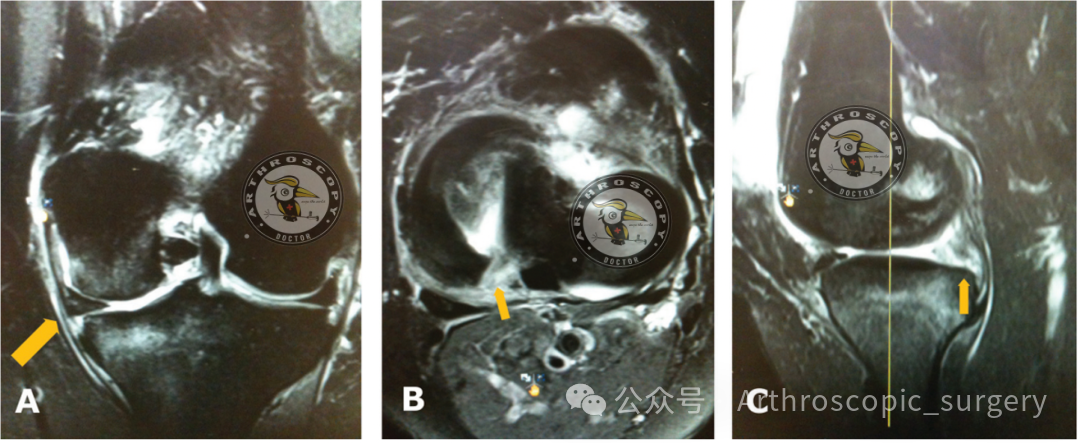

内侧半月板外突是MRI诊断MMRTs可靠且有用的征象。

“鬼影征(Ghost sign)”是MRI诊断MMRTs可靠且有用的征象。

“截断征”(多见于冠状位MRI)是MRI诊断MMRTs可靠且有用的征象。

内侧半月板根部附着处(胫骨平台后内侧)的骨髓水肿,可作为MRI诊断MMRTs的参考征象。